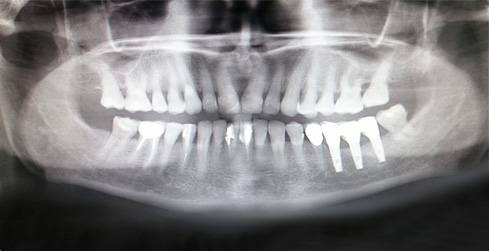

Клинический случай 4. Использование направляющего параллельности сверления

Д.м.н., проф. Мушеев И.У.Д.м.н., проф. Мушеев И.У.

1) Панорамный снимок, пациентка 62 года, отсутствуют 36 и 37 зубы, планируется имплантация 3-х имплантатов в области отсутствующих зубов.

2) Состояние перед имплантацией.